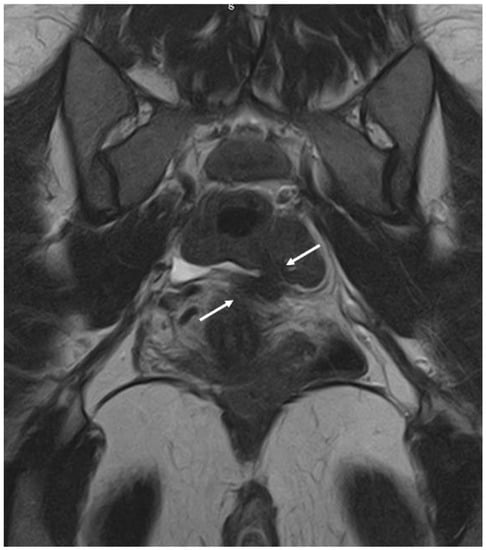

- Bazot, M.; Gasner, A.; Ballester, M.; Daraï, E. Value of thin-section oblique axial T2-weighted magnetic resonance images to assess uterosacral ligament endometriosis. Hum. Reprod. 2010, 26, 346–353. [Google Scholar] [CrossRef]